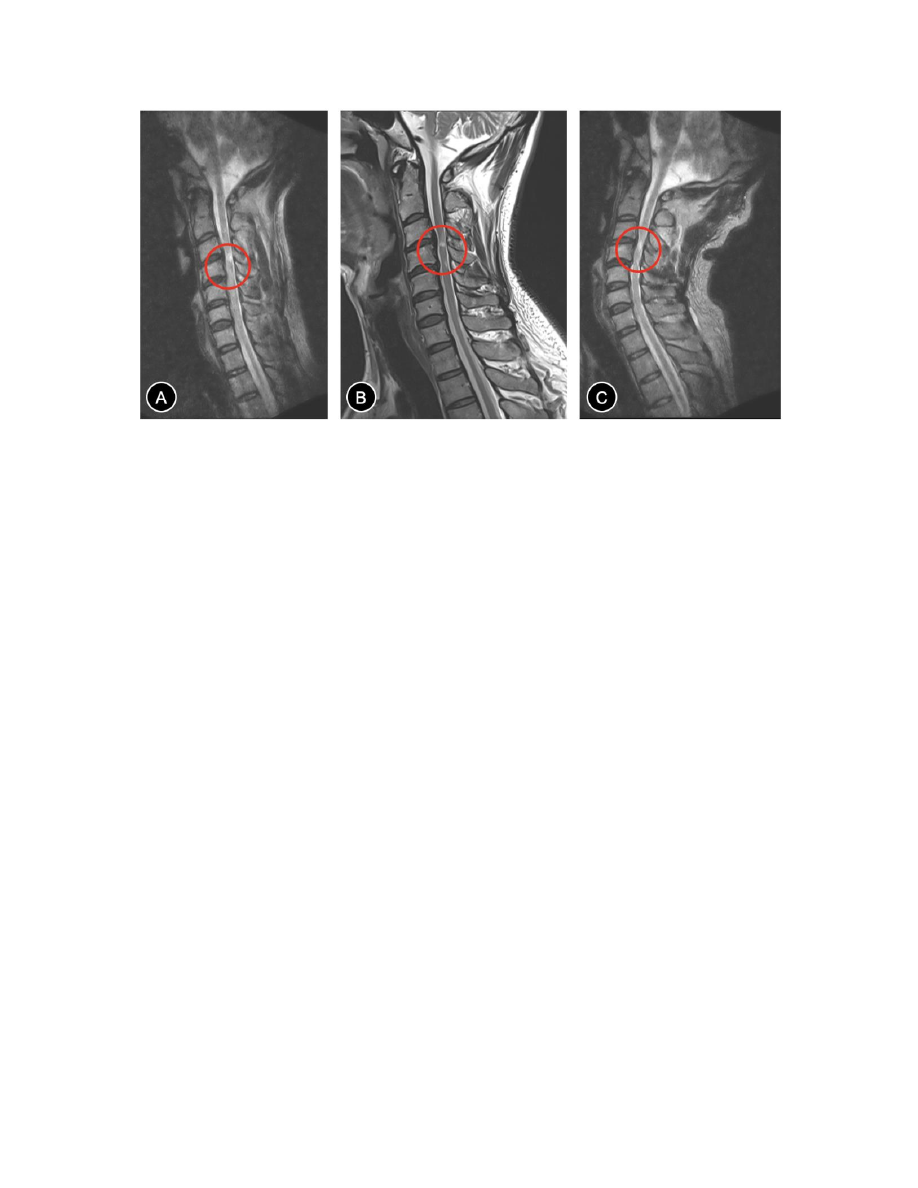

2

:不同体位颈椎

MRI

检查结果对比

A.

颈椎过屈位

B.

颈椎中立位

C.

,相比于过屈和中立位,

C3-5

水平脊髓明显受压